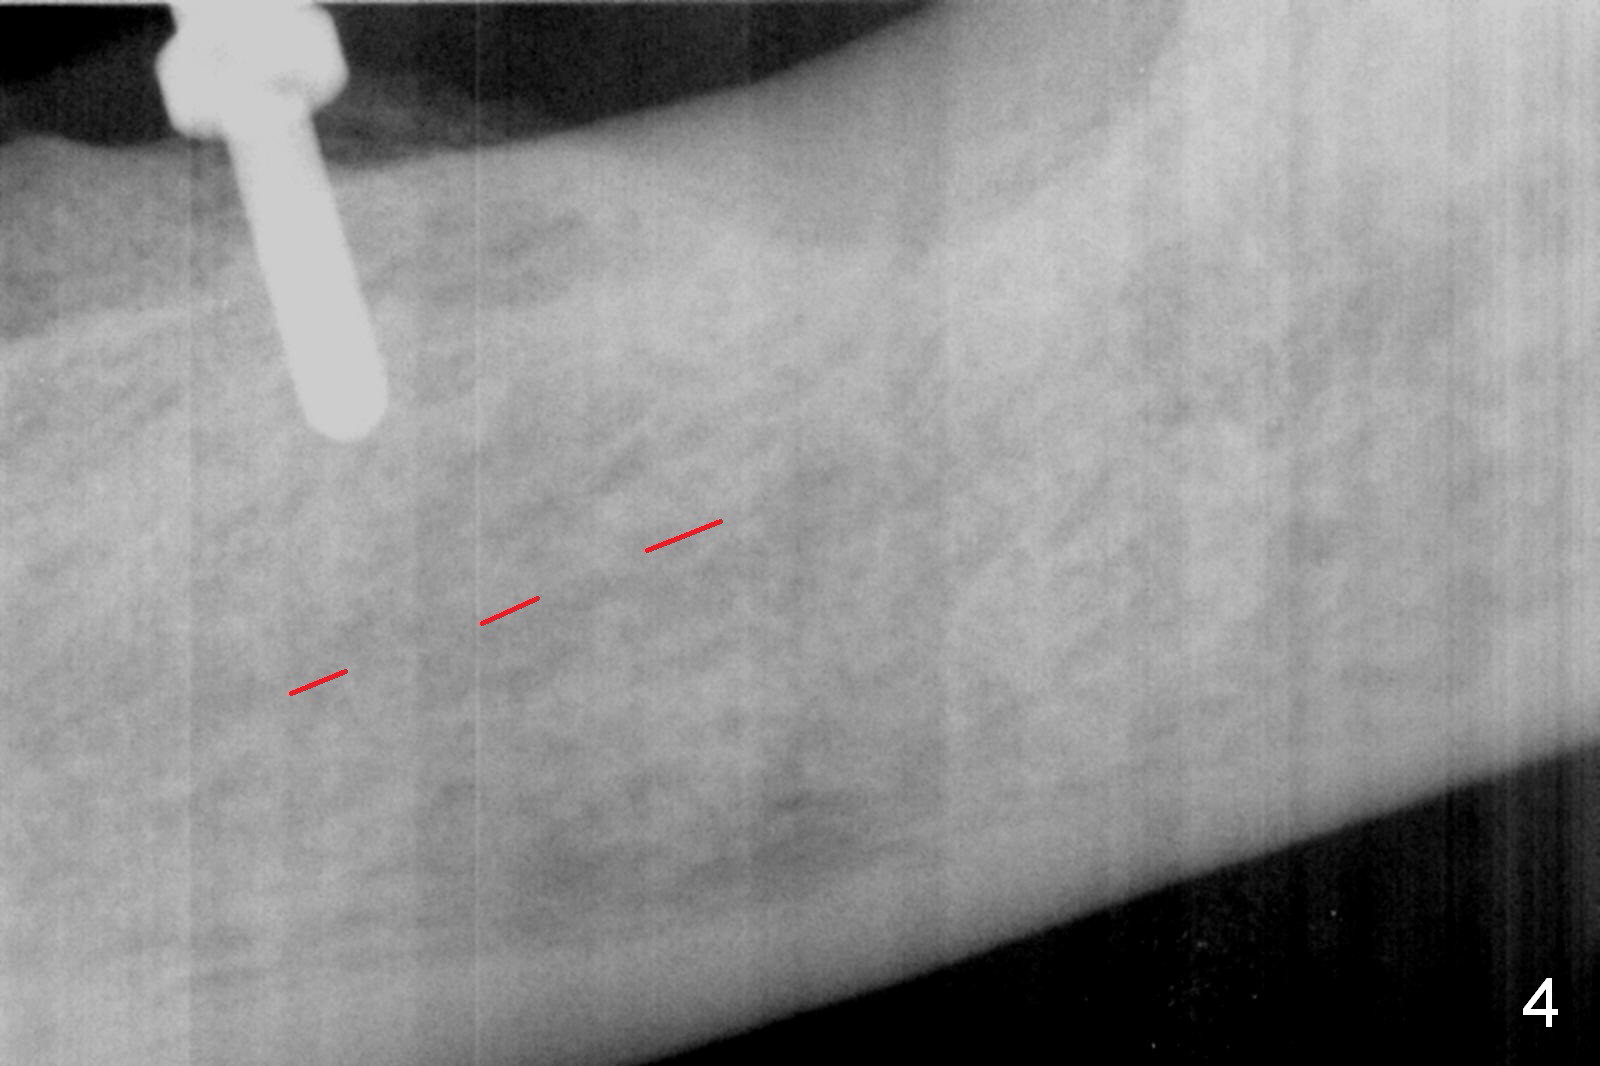

Except the tooth #30, the patient is completely edentulous (Fig.1,2). His chief complaint is "food gets into the missing tooth area". Due to short guide pin (Fig.3) and parallel pin (Fig.4), it is difficult to calculate precisely at the site of #19 the distance to the superior border of the Inferior Alveolar Canal (Fig.4 red dashed line). The clearance appears to be limited when a 4.3 mm drill is in place with 11 mm depth (Fig.5). Therefore an implant shorter than the last drill is placed (5x9 mm, Fig.6). Insertion torque is >50 Ncm. A 5x4(2) mm pair abutment is inserted temporarily to check occlusion with the opposing dentition (A). Finally a 5x2 mm healing abutment is placed with harvested autogenous bone placed between the implant and abutment (Fig.7). Before discharging the patient, the lower RPD is in place to check the position of the implant/abutment (Fig.8).